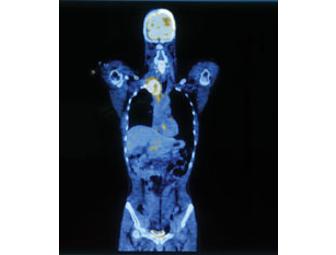

An extremely rare opportunity to spend the "day" with noted Chief of Nuclear Medicine and PET Imaging, David K. Shelton, MD. Dr. Shelton will personally lead you on a behind the scenes tour of UC Davis Medical Center. Whether brain scans or whole body imaging, he will show you cutting edge medical technology for diagnostics and treatment and talk to you about the future of medicine. Dr. Shelton is also professor of radiology and nuclear medicine at the University of California, Davis, School of Medicine and recently completed a "tour of duty" as Chief of Staff.

Dr. Shelton specializes in diagnostic radiology, including CT, MRI and percutaneous lung biopsies. He is studying cardiothoracic radiology, nuclear medicine, computer networking systems in nuclear radiology, functional cardiac protocols, and tumor work-up staging of functional imaging. Dr. Shelton pioneered the development of transesophageal echocardiography, and has presented nationally on osteoporosis, skeletal metastases in lung cancer patients, thyroid carcinoma, cardiovascular MRI and SPECT. He also has authored eight radiology textbook chapters and reviews for the Western Journal of Medicine and the Journal of Thoracic Imaging.